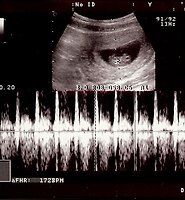

16주 3일 초음파사진 본문

정말 많이컷네~

10.3cm ^^

허벅지와 관절들도 보이고, 머리도 ^^

건강하게 잘자라~ 사랑해~♡